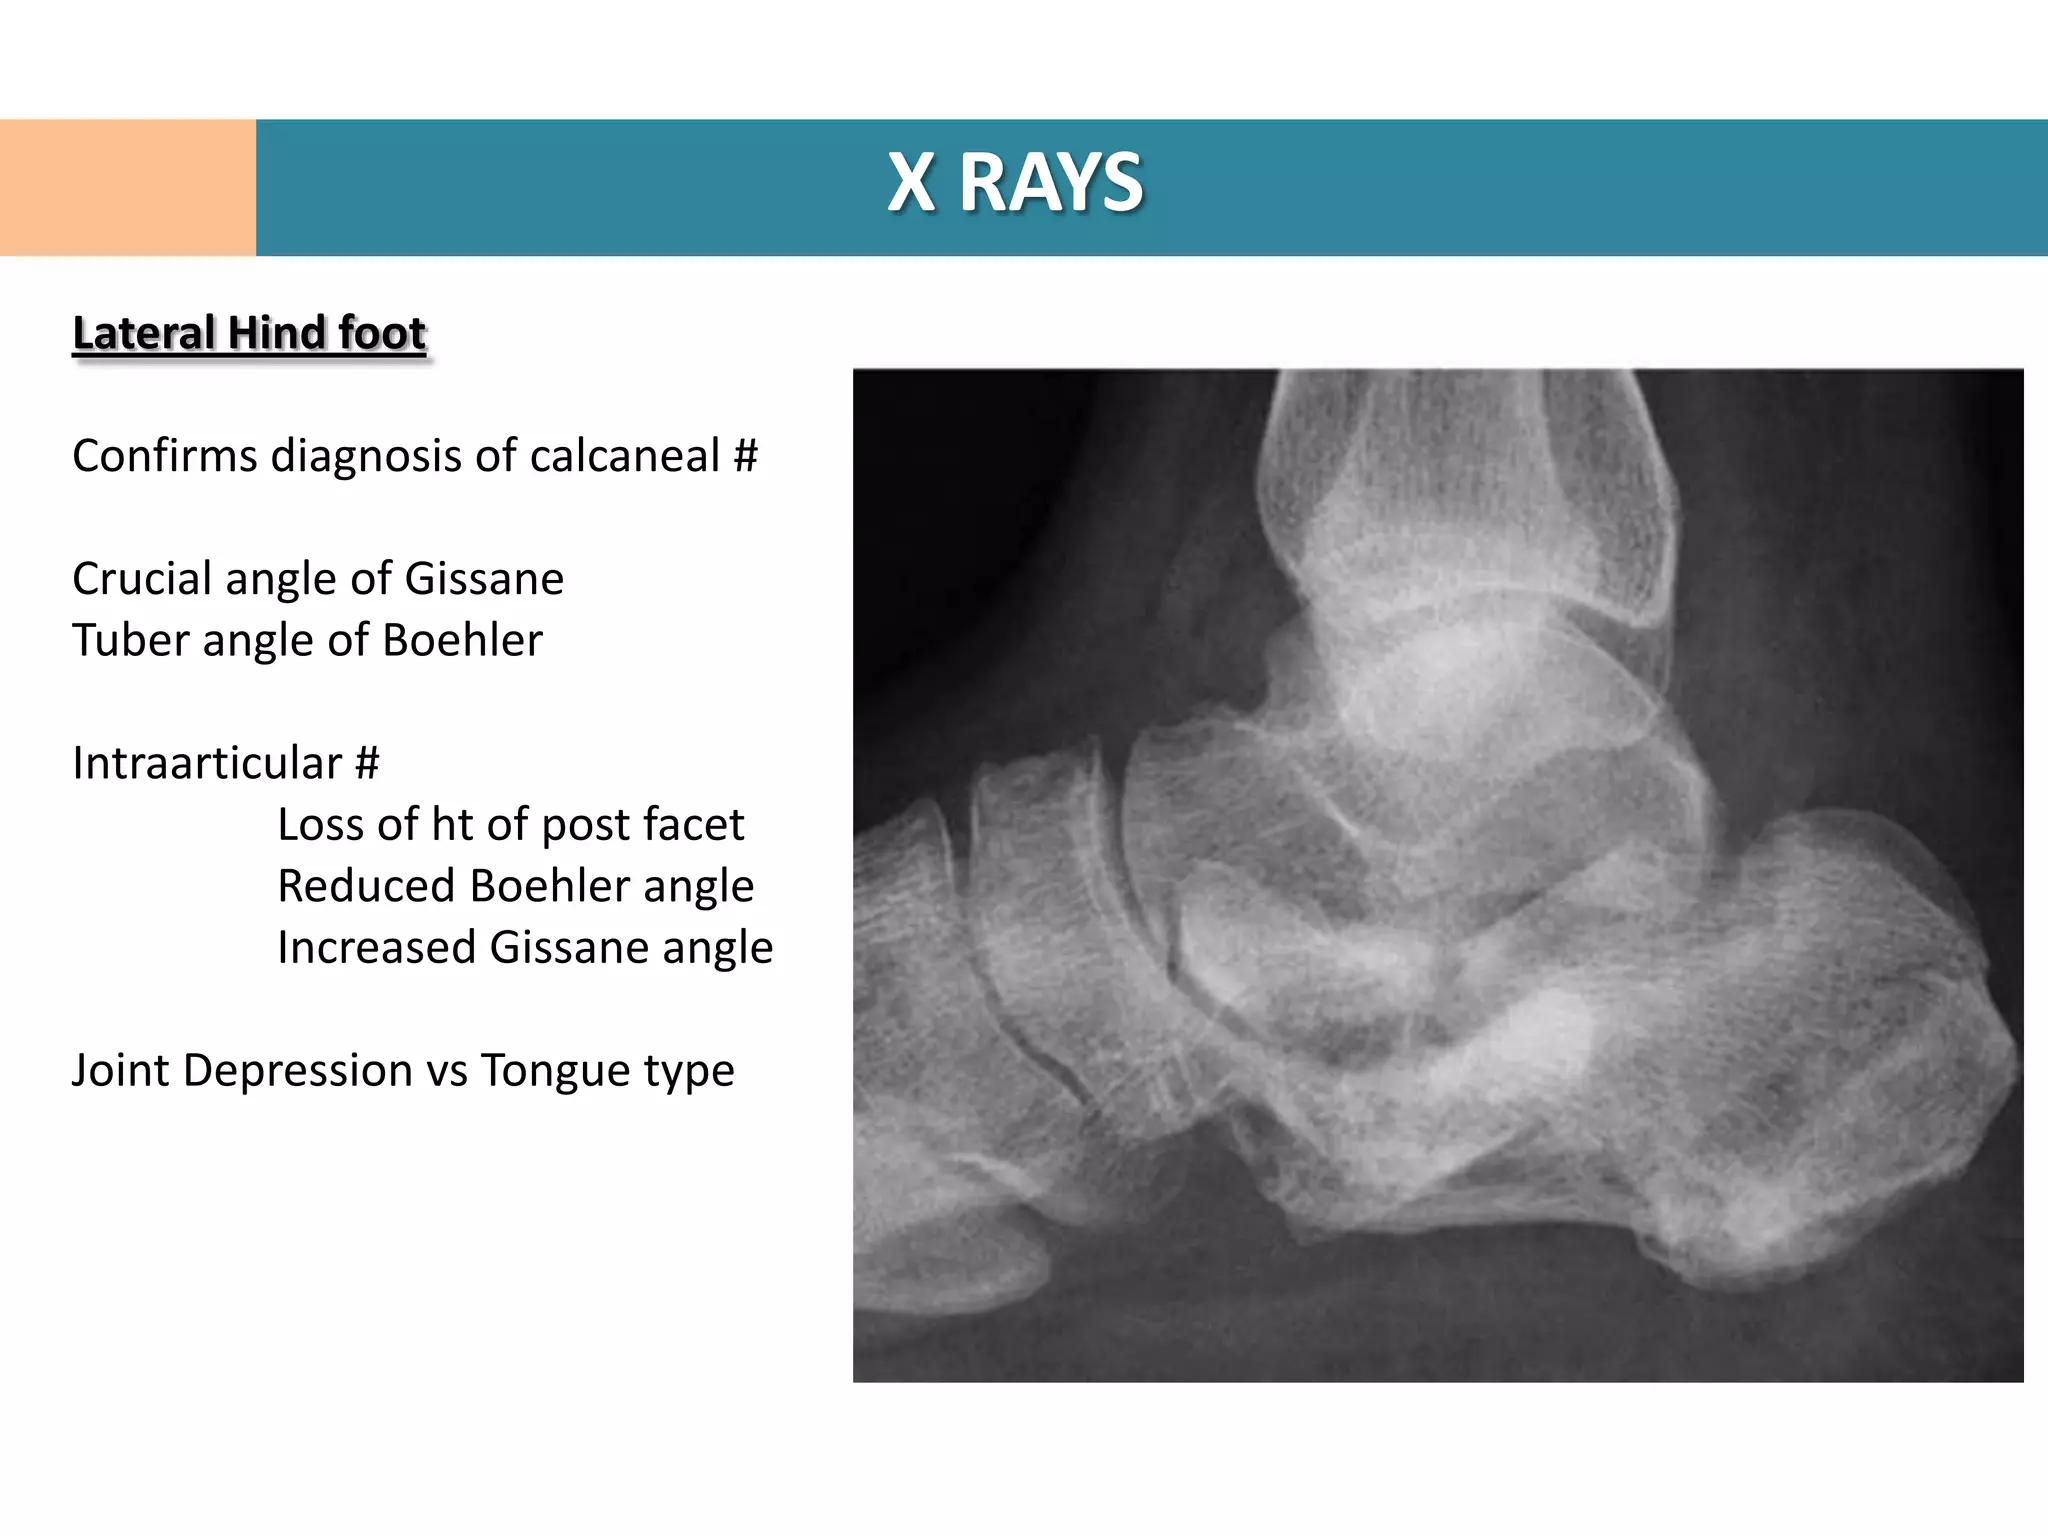

Lateral Hind foot

Confirms diagnosis of calcaneal #

Crucial angle of Gissane

Tuber angle of Boehler

Intraarticular #

Loss of ht of post facet

Reduced Boehler angle

Increased Gissane angle

Joint Depression vs Tongue type